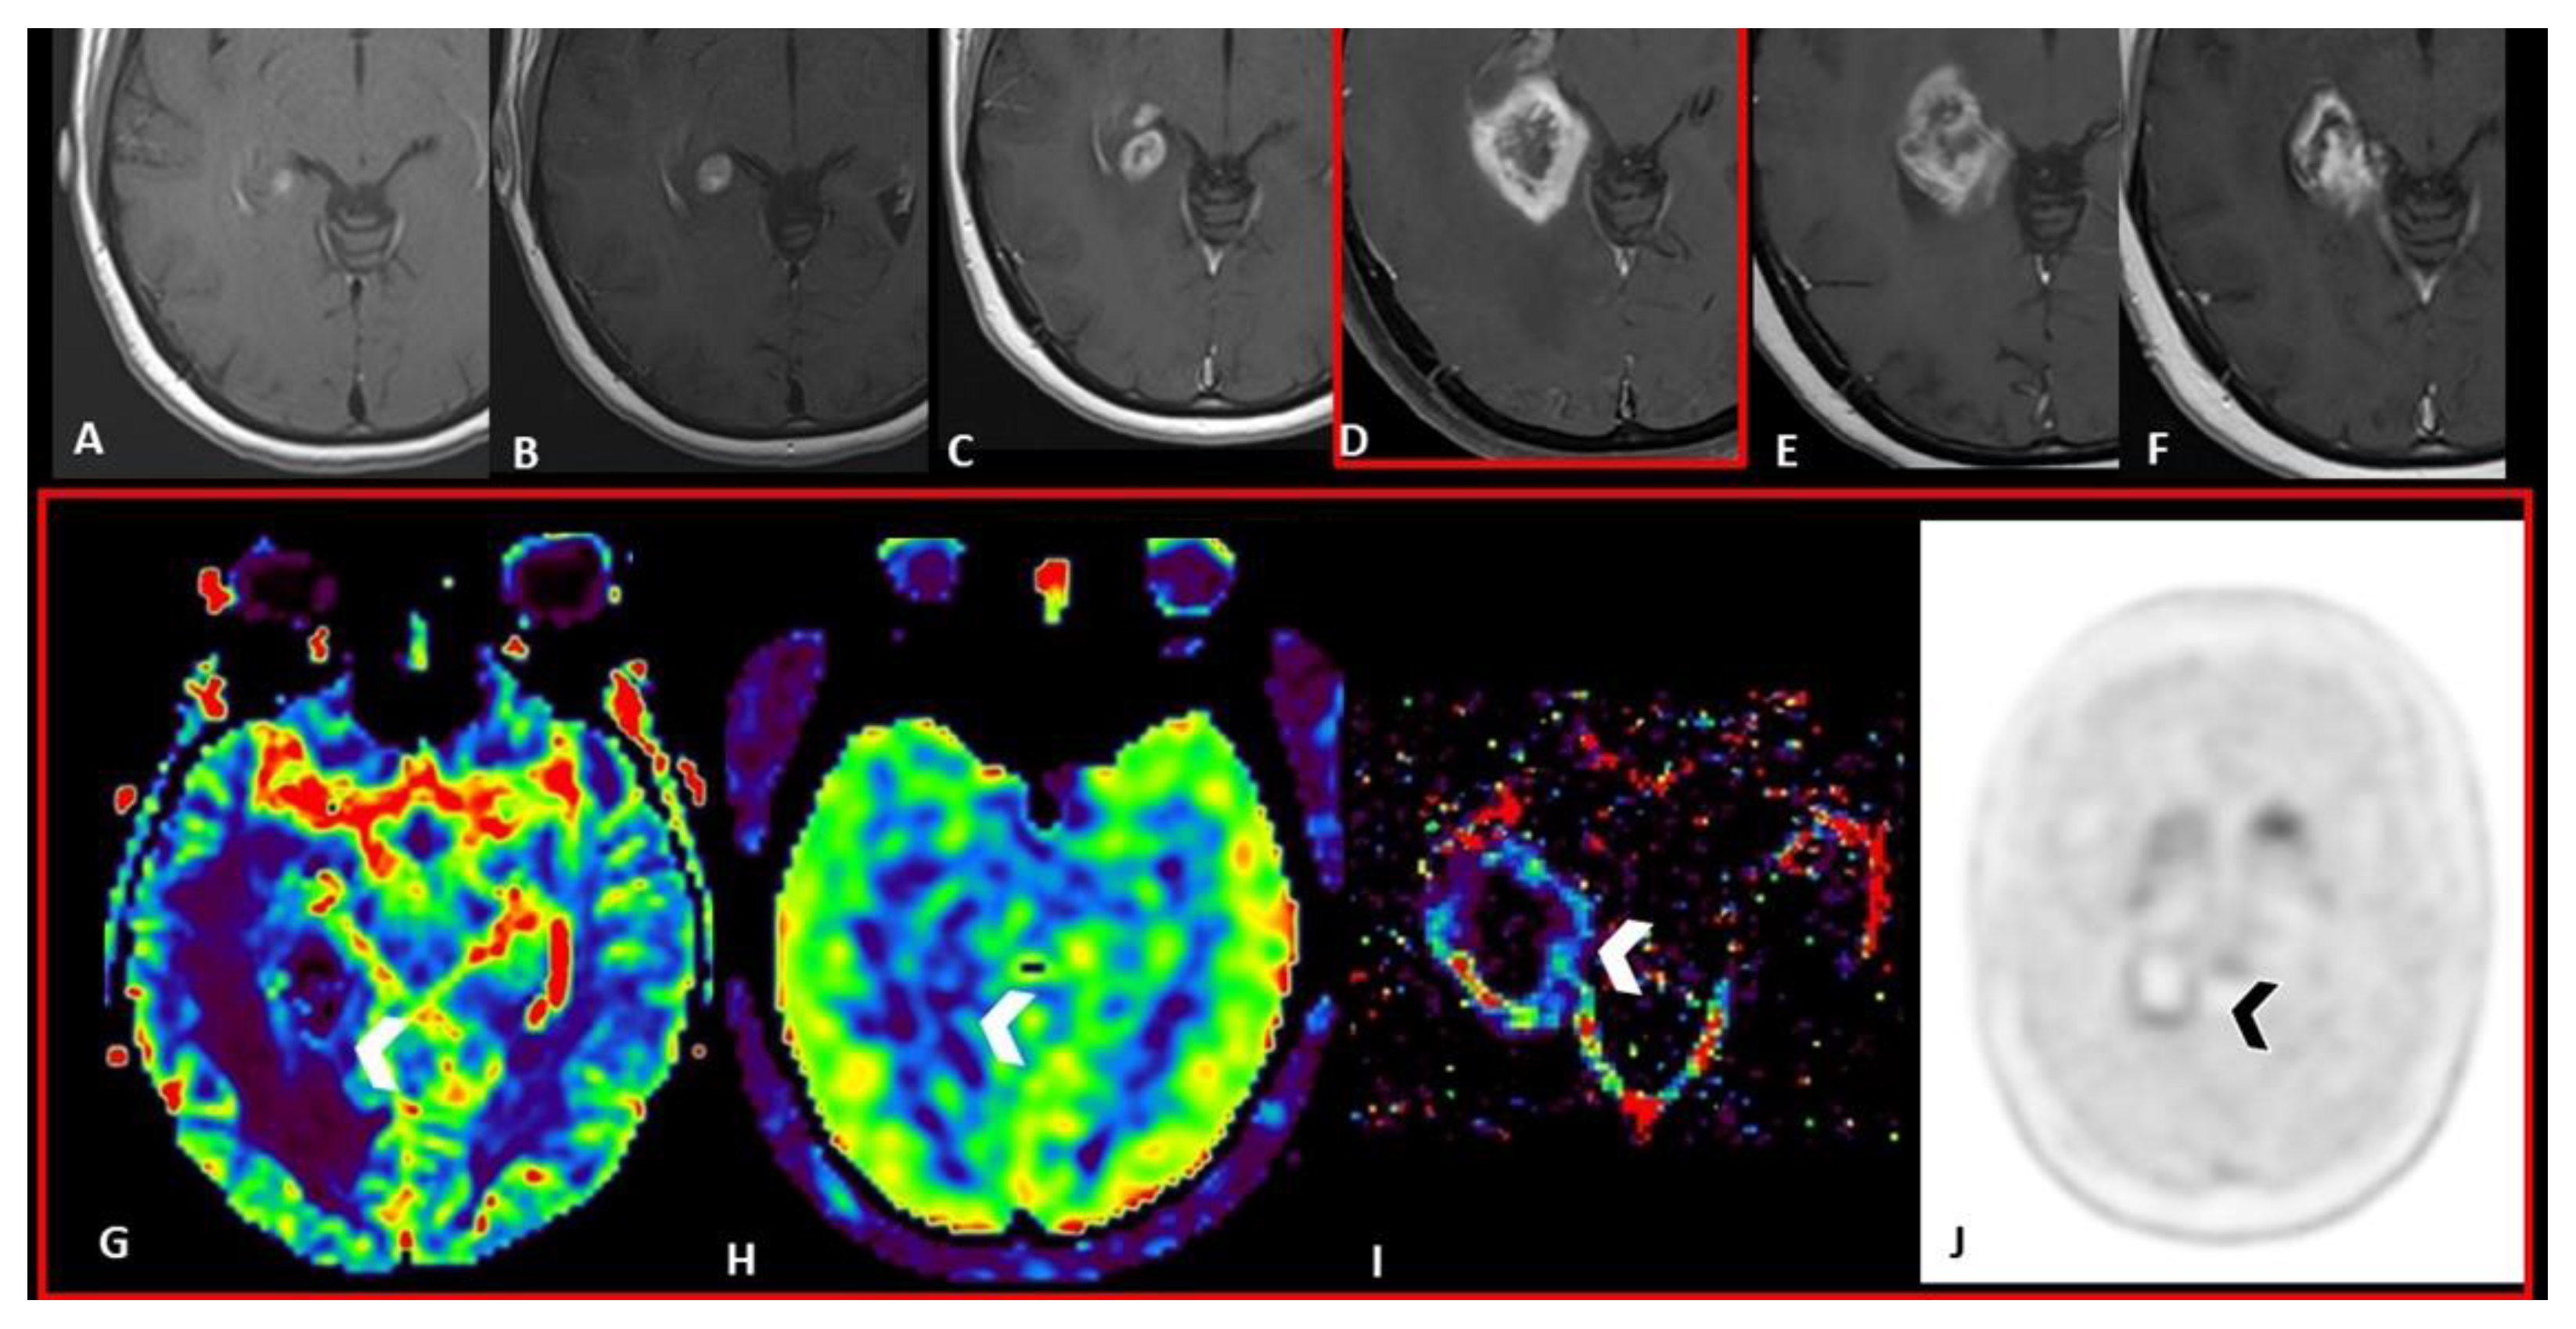

- An enhancing lesion may represent both tumor recurrence and post-treatment radiation effects; T1 mapping could help in differential diagnosis with continuous but slow accumulation of contrast agent in RN in contrast to the rapid contrast agent accumulation and relatively fast clearance in tumor recurrence.

4.1. Post-Contrast T1-Weighted Sequences

- Wang, B.; Zhang, Y.; Zhao, B.; Zhao, P.; Ge, M.; Gao, M.; Ding, F.; Xu, S.; Liu, Y. Postcontrast T1 Mapping for Differential Diagnosis of Recurrence and Radionecrosis after Gamma Knife Radiosurgery for Brain Metastasis. Am. J. Neuroradiol. 2018, 39, 1025–1031. [Google Scholar] [CrossRef]

- Zach, L.; Guez, D.; Last, D.; Daniels, D.; Grober, Y.; Nissim, O.; Hoffmann, C.; Nass, D.; Talianski, A.; Spiegelmann, R.; et al. Delayed contrast extravasation MRI: A new paradigm in neuro-oncology. Neuro-Oncol. 2015, 17, 457–465. [Google Scholar] [CrossRef]